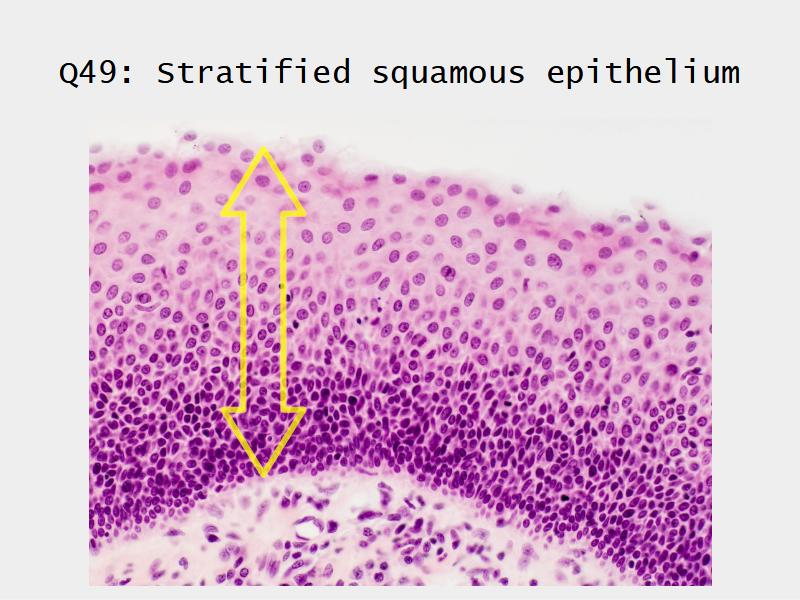

What cells are present?

Slides: Respiratory System

- Slide 71: Nostril

- Slide 72 & 74: Lung

- Slide 73: Trachea

- Slide 108: Olfactory epithelium

- Slide 111: Epiglottis